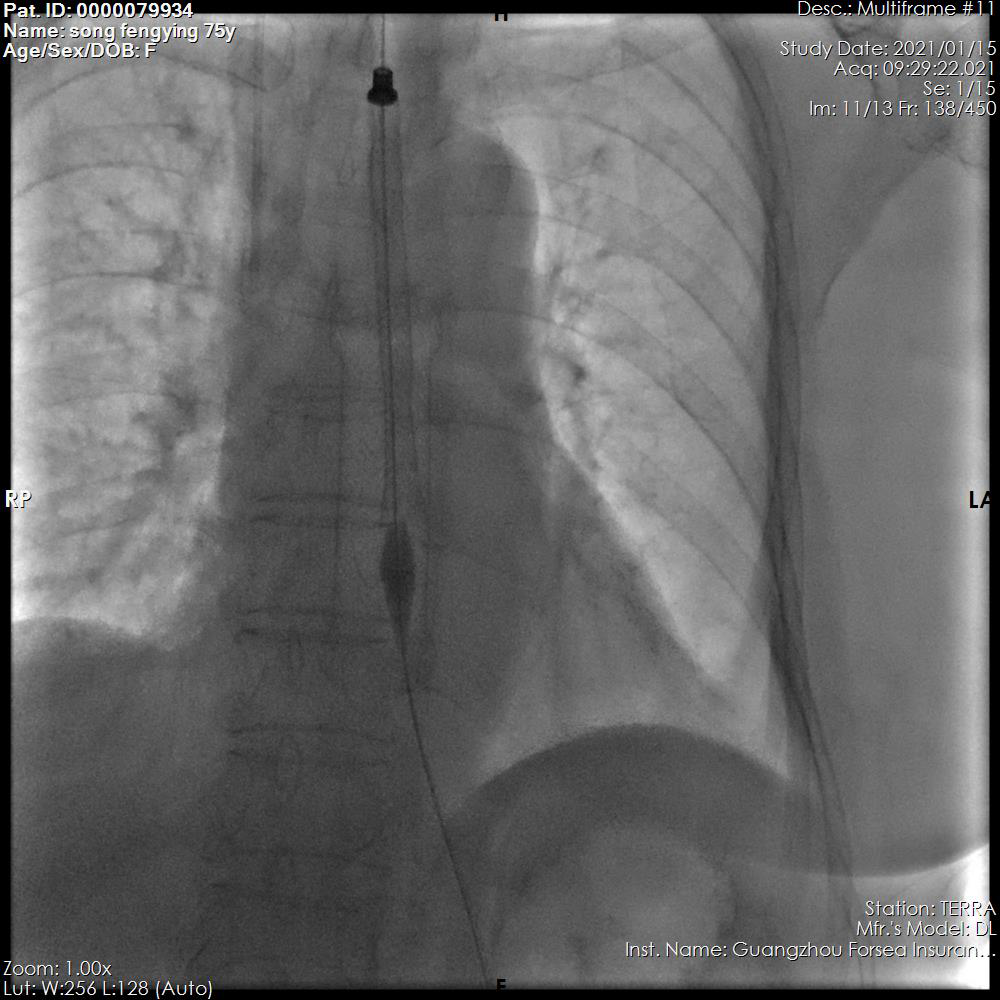

支架经推送器放至狭窄部位

经过周密的术前准备,惠雨医生和刘成旭医生在介入手术室的密切配合下,仅用 30 分钟就完成了前海人寿广州总医院首例食管支架植入手术,患者术后恢复良好。

支架释放成功